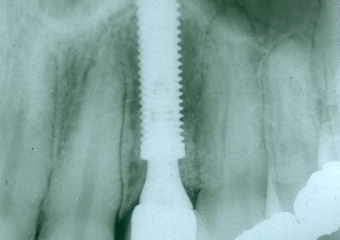

Raio X após mesialização da raiz do dente 22